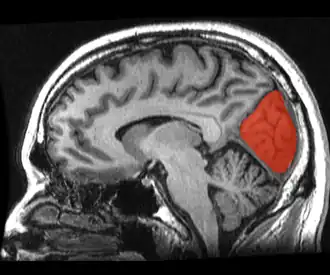

Sagittal MRI slice with the cuneus and lingual gyrus shown in red.